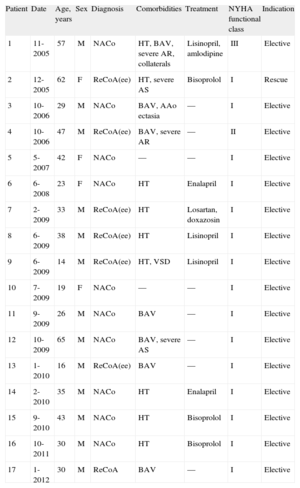

RESULTSOver a period of 7 years, we conducted 17 CS procedures in 13 men and 4 women with a mean age of 35 (15) years (range 14-65 years). Seven patients had a bicuspid aortic valve and 1 patient had a small muscular ventricular septal defect (patient 9, Table 1). Five patients had a second cardiac surgery pending: 2 for aortic regurgitation, 2 for stenosis, and 1 for annuloaortic ectasia. Nine patients were treated for hypertension and 15 patients were in New York Heart Association (NYHA) class I, 1 was in NYHA class II, and 1 was in NYHA class III (Table 1).

Clinical Characteristics of Patients (Mean Age 35.0 [15.2] Years)

| Patient | Date | Age, years | Sex | Diagnosis | Comorbidities | Treatment | NYHA functional class | Indication |

| 1 | 11-2005 | 57 | M | NACo | HT, BAV, severe AR, collaterals | Lisinopril, amlodipine | III | Elective |

| 2 | 12-2005 | 62 | F | ReCoA(ee) | HT, severe AS | Bisoprolol | I | Rescue |

| 3 | 10-2006 | 29 | M | NACo | BAV, AAo ectasia | — | I | Elective |

| 4 | 10-2006 | 47 | M | ReCoA(ee) | BAV, severe AR | — | II | Elective |

| 5 | 5-2007 | 42 | F | NACo | — | — | I | Elective |

| 6 | 6-2008 | 23 | F | NACo | HT | Enalapril | I | Elective |

| 7 | 2-2009 | 33 | M | ReCoA(ee) | HT | Losartan, doxazosin | I | Elective |

| 8 | 6-2009 | 38 | M | ReCoA(ee) | HT | Lisinopril | I | Elective |

| 9 | 6-2009 | 14 | M | ReCoA(ee) | HT, VSD | Lisinopril | I | Elective |

| 10 | 7-2009 | 19 | F | NACo | — | — | I | Elective |

| 11 | 9-2009 | 26 | M | NACo | BAV | — | I | Elective |

| 12 | 10-2009 | 65 | M | NACo | BAV, severe AS | — | I | Elective |

| 13 | 1-2010 | 16 | M | ReCoA(ee) | BAV | — | I | Elective |

| 14 | 2-2010 | 35 | M | NACo | HT | Enalapril | I | Elective |

| 15 | 9-2010 | 43 | M | NACo | HT | Bisoprolol | I | Elective |

| 16 | 10-2011 | 30 | M | NACo | HT | Bisoprolol | I | Elective |

| 17 | 1-2012 | 30 | M | ReCoA | BAV | — | I | Elective |

AAo, ascending aorta; AR, aortic regurgitation; AS, aortic stenosis; BAV, bicuspid aortic valve; F, female; HT, hypertension; M, male; NACo, native aortic coarctation; NYHA, New York Heart Association; ReCoA(ee), recoarctation of the aorta with previous end-to-end anastomosis; VSD, ventricular septal defect.